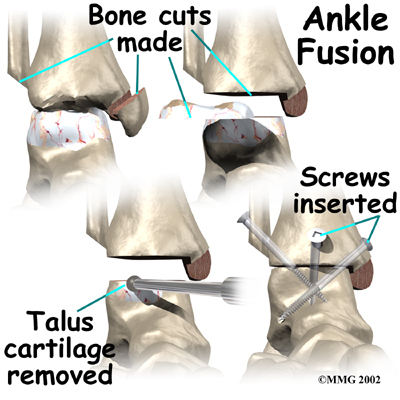

Because no one wants to lose the ability to move the ankle, much research has been done trying to perfect an

Because no one wants to lose the ability to move the ankle, much research has been done trying to perfect an